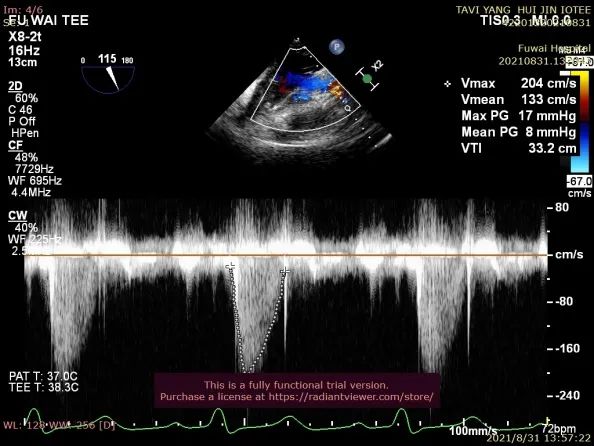

术后即刻放射线显示人工瓣膜位置良好,随心跳运动,与周围组织无相对位移;TEE显示人工主动脉瓣金属支架位置良好,瓣环下支架长度约7mm,支架自膨后外径为26.8mm,接近瓣膜真实外径(图6),CDFI多角度观察,舒张期冠脉开口处血流通畅,左室流出道侧人工瓣和自体瓣环之间仅见微量反流信号(图7),收缩期人工瓣口流速良好(峰值流速:2.0m/s,峰值压差:17mmHg)(图8)。

图8. TEE(胃底心尖五腔心切面)提示人工瓣形态位置良好,CW:Vmax=2.0m/s,MaxPG=17mmHg